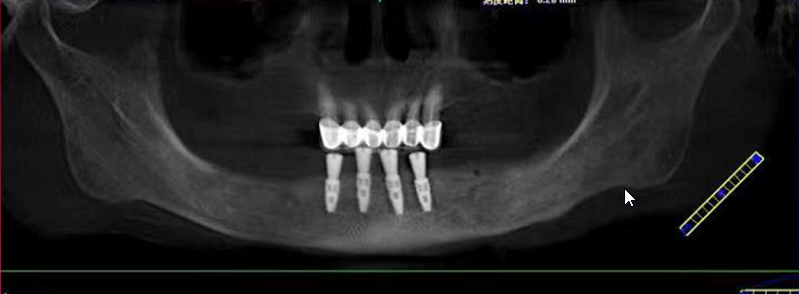

姚江武院长来为大家分享顾客术前牙片情况及种植方案。并现场讲解数字化全程导板种植技术与传统种植牙的区别和优势。

传统种植牙手术,被称为“自由手种植牙”,需要种植医生具备丰富的临床经验,从而准确判断种植牙植入牙槽骨的角度、深度。而数字化种植牙,通过制作数字化种植导板,导航辅助种牙,引导种植体精准植入,不仅创口小更舒服,而且避免盲种,吻合度更高,使种牙全程精准、微创,轻松享受缺牙重生的乐趣。